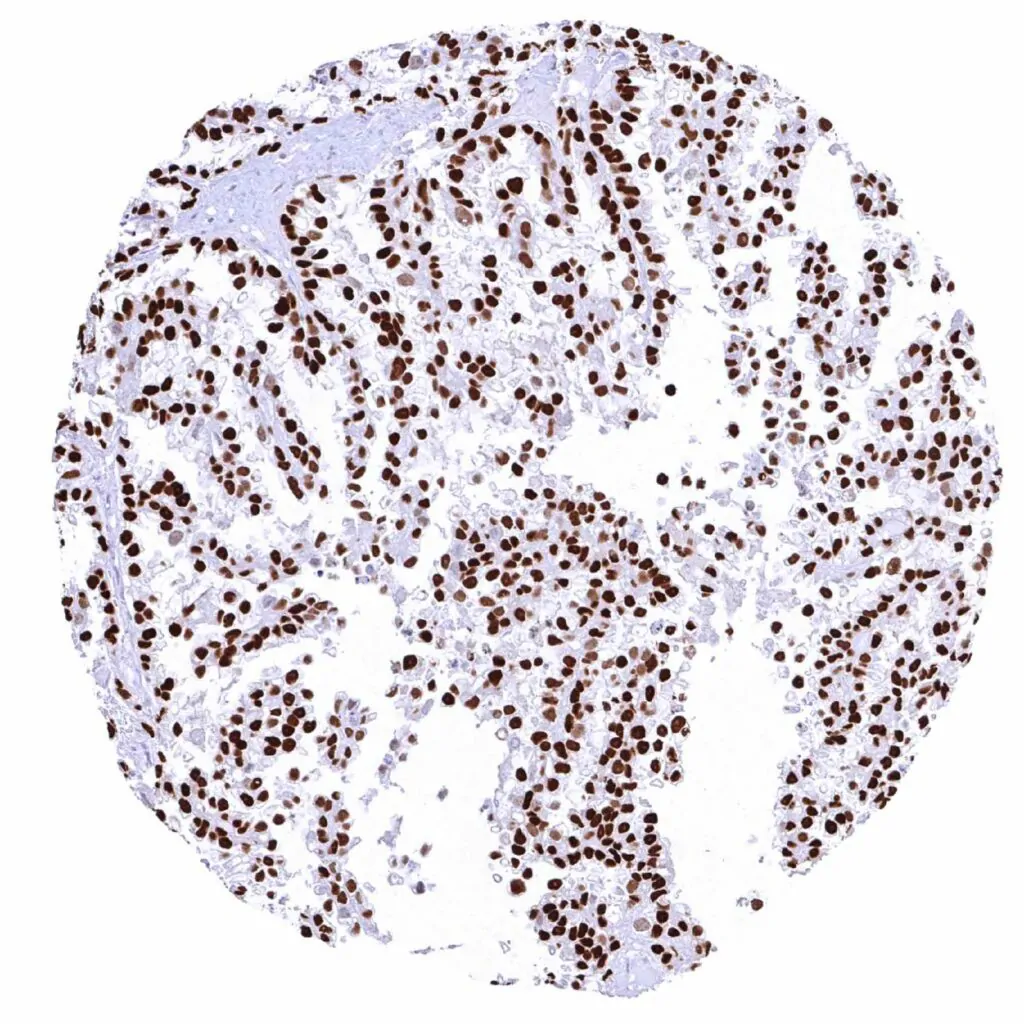

Ovary – Clear cell carcinoma with strong Cyclin E1 staining of all tumor cells